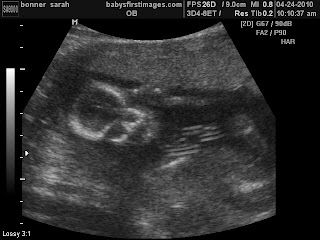

We had our 20 week appt on Thursday and Baby B is looking perfect! We saw all his organs and arms, legs, hands and feet! He was quite the wiggle worm and the u/s tech had to really try hard to get his profile picture....but she got it! And OMG he looks like his daddy! I keep staring at the picture thinking about getting to meet him soon!

*How big is baby?: 10 inches long and weighing about 10 oz (a little more than 1/2 lb) The size of a banana